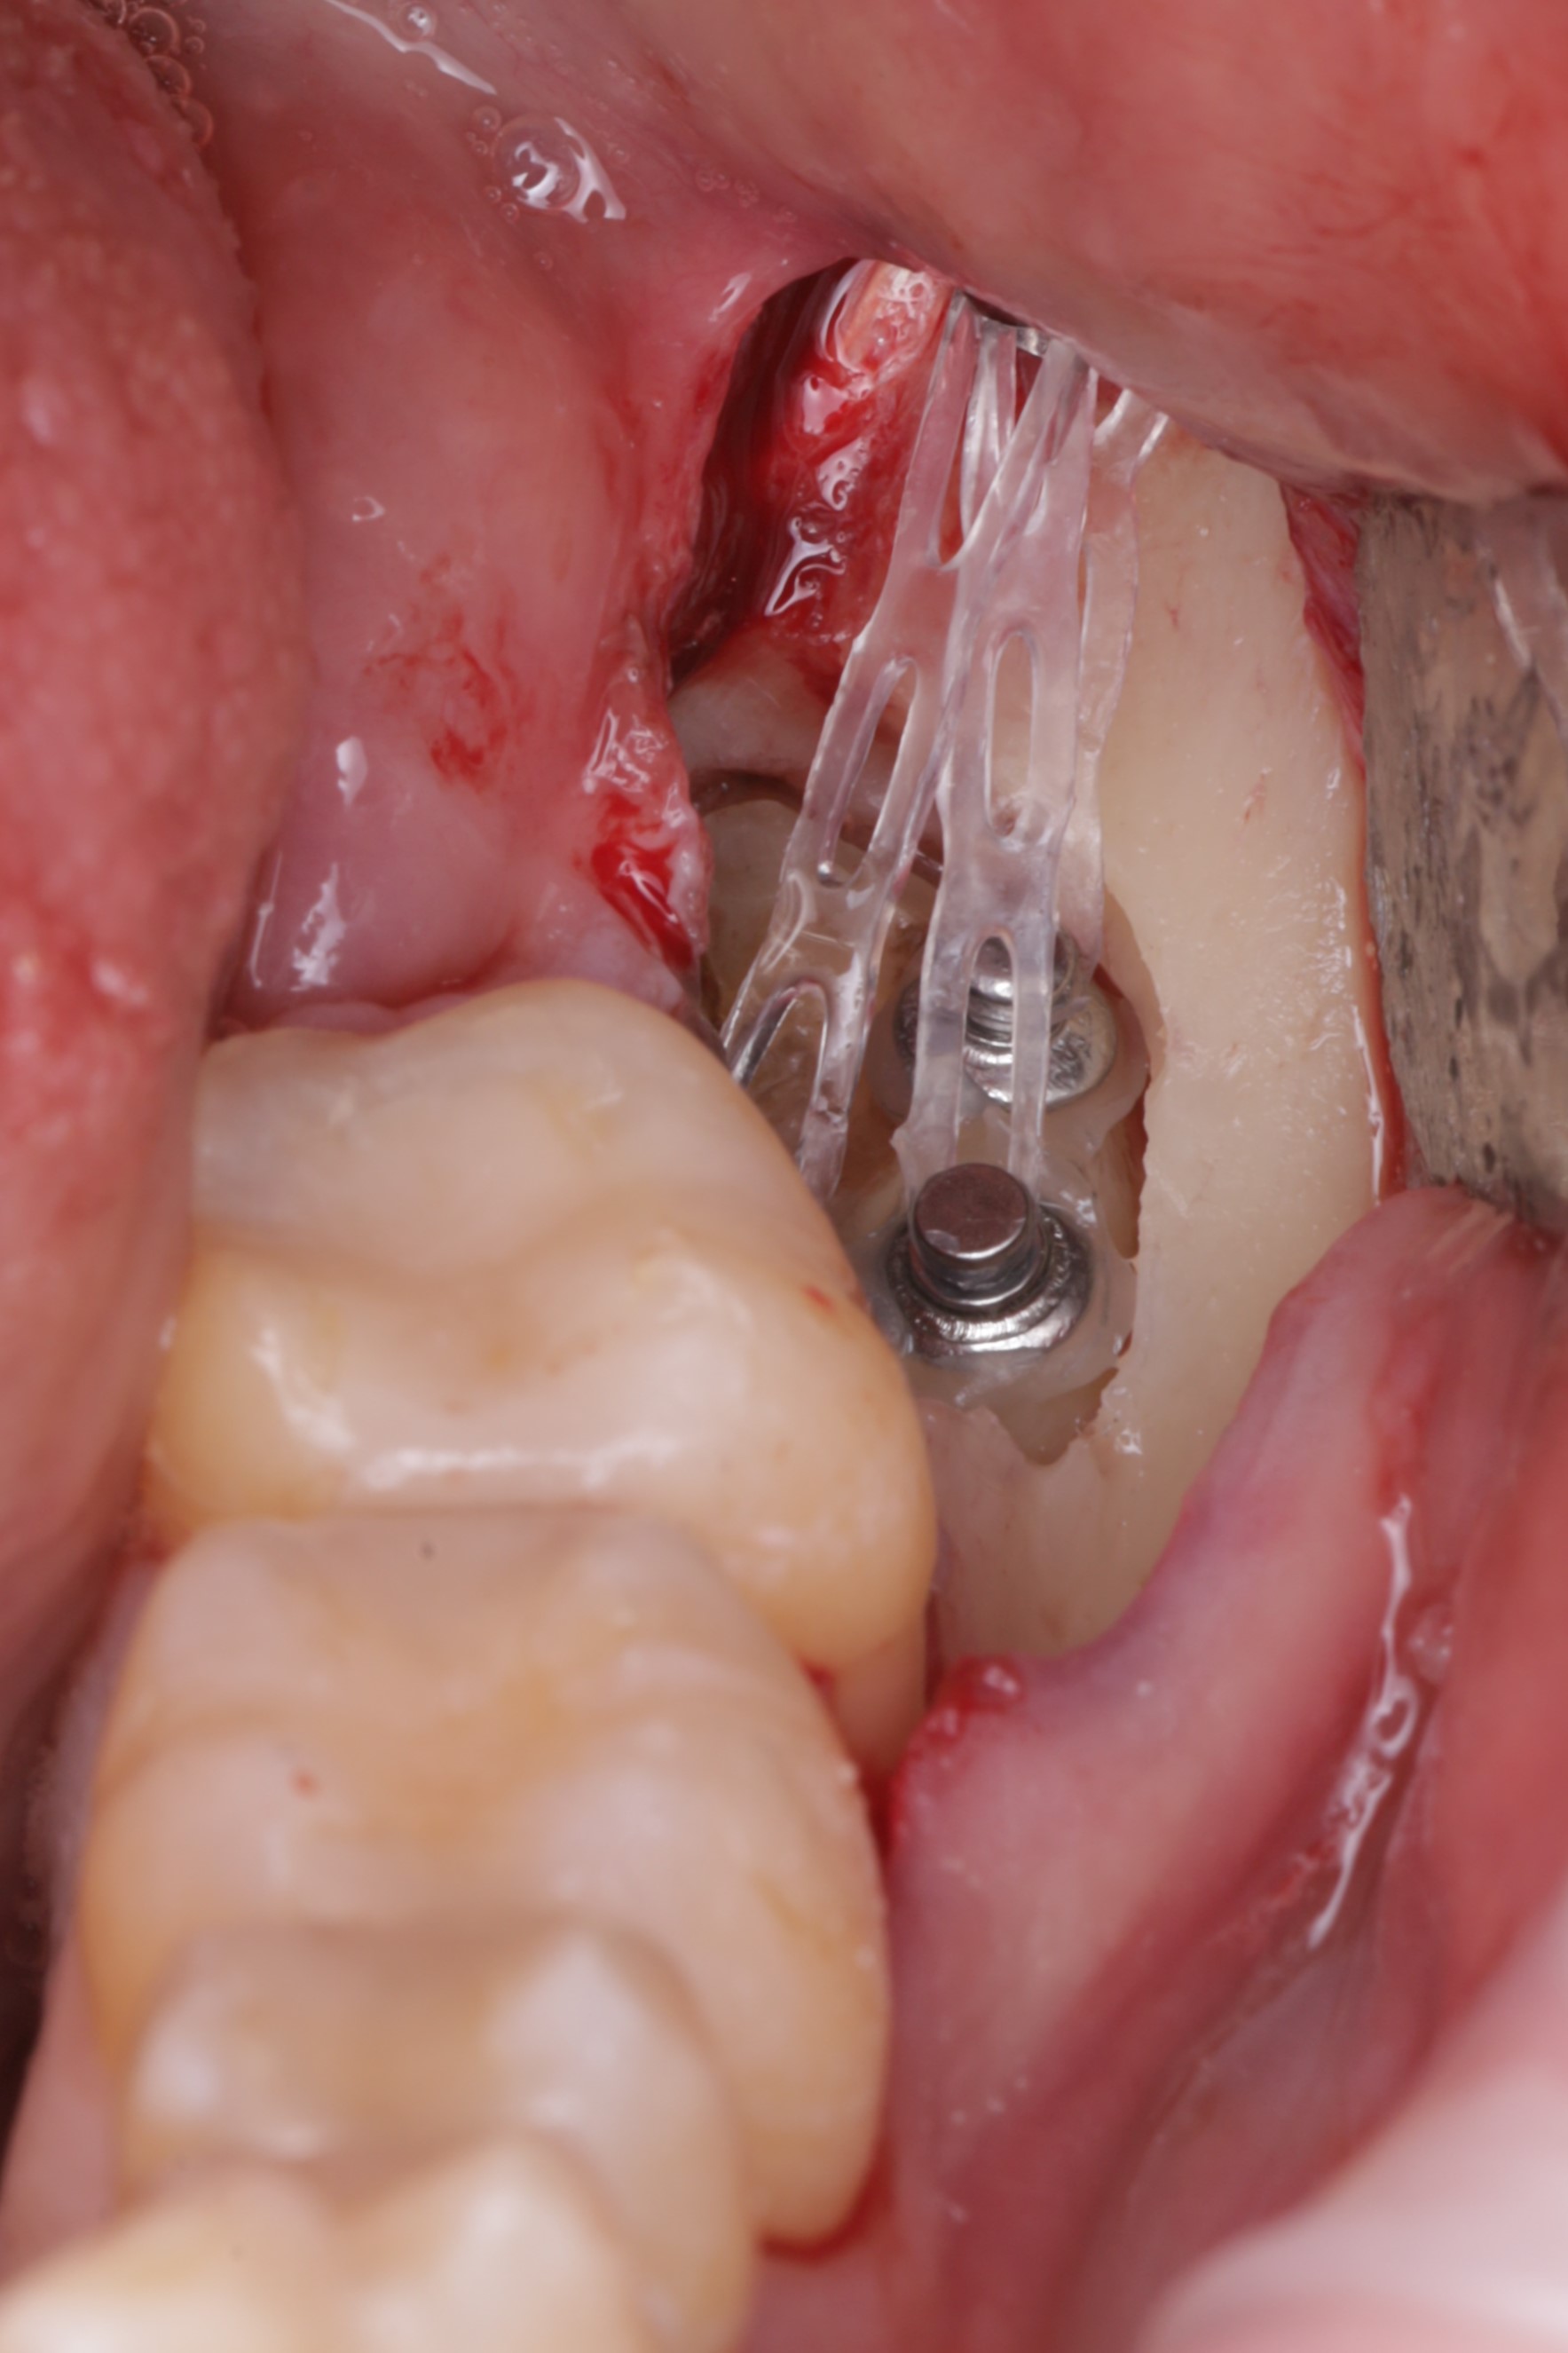

Установлен ортодонтический минивинт и три кнопки

Произвдена активация с помощью ортодонтичечских тяг